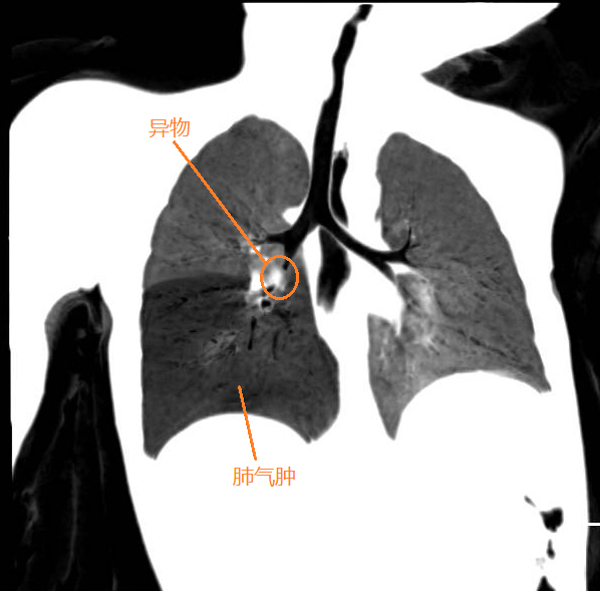

据悉,患儿在家吃橘子后出现烦躁、哭闹,拒食的表现,便来到我院就诊,耳鼻咽喉科韦顺莲医师接诊时发现小朋友的精神萎靡,呼吸稍急促,右下肺呼吸音减弱,而且近一周还有间断的咳嗽症状。凭借多年的临床经验让韦医师一下子警惕起来,第一时间安排患儿做肺部CT及血常规检查,CT显示患儿的右侧二级支气管有低密度影,右下肺气肿,原来是气管中有异物。1岁幼儿该位置的气管直径只有4-7mm,一旦阻塞就很容易引起肺炎,现在已经出现肺气肿,说明气管内已经大部分被阻塞,情况十分危急。